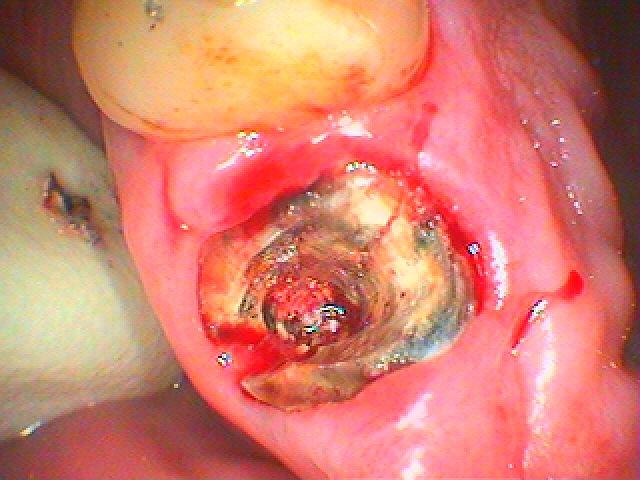

前歯部のブリッジがグラグラ診てほしい 審美領域のインプラント治療の臨床現場|お知らせ |広島市安佐南区の歯科医院 前歯部のブリッジがグラグラ診てほしい 審美領域のインプラント治療の臨床現場 トップ お知らせ・ブログ お知らせ 前歯部のブリッジがグラグラ診てほしい 審美領域のインプラント治療の臨床現場 前歯部のブリッジがグラグラ診てほしい 審美領域のインプラント治療の臨床現場 術前のパノラマになります デンタルレントゲンになります 左上の2番部 右上の1番部のデンタルレントゲンになります 左上の2番 被せを外していきました 左上の2番部は歯が割れていました 右上の1番部は抜歯即時インプラントを行っていきます 抜歯即時インプラント時になります Web診療予約 初めての方へ 選ばれ続ける理由 院内設備について 歯が痛いしみる一般歯科 歯がぐらぐらする歯周病 健康な歯を保ちたい予防歯科 子供の虫歯予防をしたい小児歯科 銀歯をセラミックに審美歯科 白い歯を目指しませんか?ホワイトニング 矯正専門医がいるので安心矯正歯科 抜けた歯を補いたいインプラント・入れ歯 医院案内 スタッフ紹介 メリィハウス歯科クリニックオフィシャルホームページ ラベンダー歯科クリニックオフィシャルホームページ お知らせ・ブログ ホーム 診療科目 一般歯科 歯周病治療 予防治療 小児歯科 審美治療 ホワイトニング 矯正歯科 入れ歯・インプラント マウスピース矯正 初めての方へ 院長・スタッフ 設備紹介 医院案内・アクセス メニューを閉じる